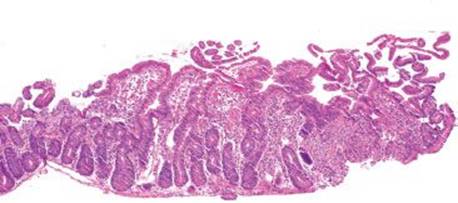

Figure 3.316 Isosporiasis. This intermediate power view shows how easy it is to miss Isospora. At low power, only gastric foveolar metaplasia and perhaps a slight increase in lamina propria eosinophils is seen. Other fields of this same case were essentially normal, emphasizing that every biopsy needs a few high power fields of attention for such extremely subtle diagnoses.

Isosporiasis is among the more common protozoan causes of severe diarrhea in AIDS patients (Figs. 3.316–3.318).190 The Isospora belli organisms are spread via contaminated water or fecal–oral contamination. They localize to the small bowel surface and are exceedingly easy to miss owing to sometimes unremarkable background mucosa and sparsely distributed organisms (Figs. 3.316–3.321). Diagnostic confirmation is facilitated through identification of the oocysts in stool samples or duodenal aspirates.191 Standard therapy consists of trimethoprim–sulfamethoxazole, which is often long term in severely immunocompromised patients.